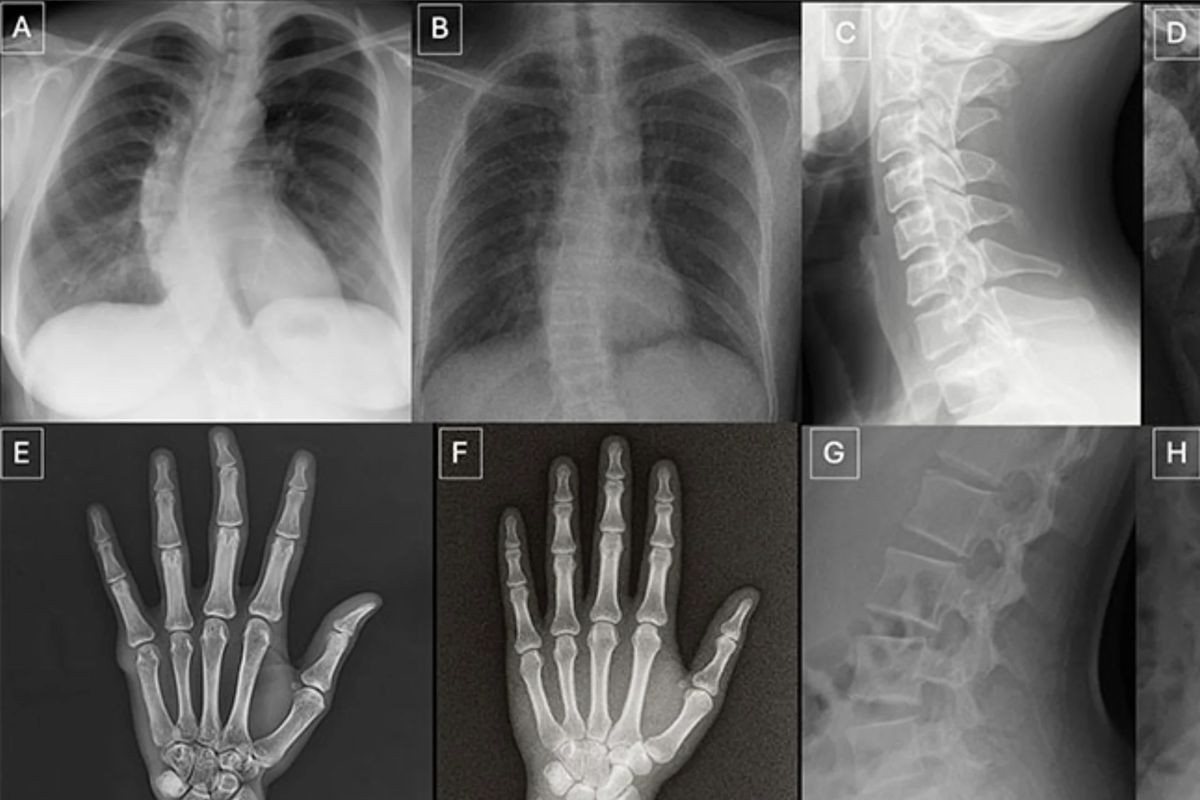

Η μελέτη, με επικεφαλής τον Δρ. Mickael Tordjman από την Ιατρική Σχολή Icahn του Mount Sinai, καταγράφει την αποτυχία 17 έμπειρων ακτινολόγων από έξι διαφορετικές χώρες να διακρίνουν σταθερά τις αυθεντικές ακτινογραφίες από τις αντίστοιχες που παρήχθησαν μέσω τεχνητής νοημοσύνης. Οι ερευνητές χρησιμοποίησαν ένα σύνολο 264 ακτινογραφιών, εκ των οποίων οι μισές ήταν πραγματικές και οι υπόλοιπες δημιουργήθηκαν μέσω του ChatGPT-4o (της OpenAI) και του εξειδικευμένου μοντέλου RoentGen.

Η μεθοδολογία της έρευνας χωρίστηκε σε διακριτές φάσεις για να μετρηθεί η αντικειμενική ικανότητα των ιατρών. Στην πρώτη φάση, οι ακτινολόγοι εξέτασαν τις εικόνες χωρίς να γνωρίζουν τον πραγματικό σκοπό της μελέτης. Όταν κλήθηκαν να αξιολογήσουν την τεχνική ποιότητα και να εντοπίσουν τυχόν ανωμαλίες, μόλις το 41% αντιλήφθηκε αυθόρμητα την παρουσία τεχνητών εικόνων. Το συγκεκριμένο εύρημα καταδεικνύει την επικίνδυνη αληθοφάνεια των παραγόμενων αρχείων.

Στη δεύτερη φάση, αφού οι ιατροί ενημερώθηκαν ότι το δείγμα περιείχε συνθετικές ακτινογραφίες, η μέση ακρίβεια διάκρισης αυξήθηκε στο 75%. Παρότι η βελτίωση είναι εμφανής, το ποσοστό αποτυχίας του 25% παραμένει απαγορευτικό για κλινικά και νομικά δεδομένα. Η ατομική απόδοση των ιατρών παρουσίασε μεγάλες διακυμάνσεις, κυμαινόμενη από 58% έως 92%. Ενδιαφέρον παρουσιάζει το γεγονός ότι η ηλικία και τα έτη προϋπηρεσίας (τα οποία έφταναν έως και τα 40 έτη) δεν αποτέλεσαν καθοριστικό παράγοντα επιτυχίας, αν και οι ακτινολόγοι με εξειδίκευση στο μυοσκελετικό σύστημα επέδειξαν ελαφρώς υψηλότερα ποσοστά αναγνώρισης.

Οι ειδικοί επισημαίνουν ότι ορισμένα τεχνικά χαρακτηριστικά προδίδουν τη συνθετική φύση αυτών των εικόνων, αν και απαιτείται εκπαιδευμένο μάτι. Οι πλαστές ακτινογραφίες συχνά παρουσιάζουν υπερβολικά λείες οστικές επιφάνειες, αφύσικη και απόλυτη συμμετρία, ατελή διακοπή του φλοιού στα κατάγματα και ενιαία μοτίβα θορύβου που δεν συναντώνται στους παραδοσιακούς αισθητήρες των ακτινολογικών μηχανημάτων.